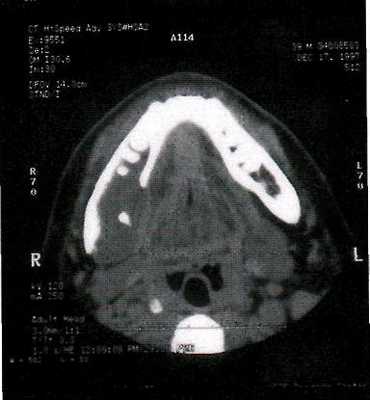

- Рентгенологическое обследование. Рентгенография и КТ челюстей, рентгенография и КТ придаточных пазух носа. Определенную диагностическую ценность может представлять сцинтиграфия, термография.

1. Компьютерная томография височно-нижнечелюстного сустава.

2. Панорамная рентгенография челюстей.